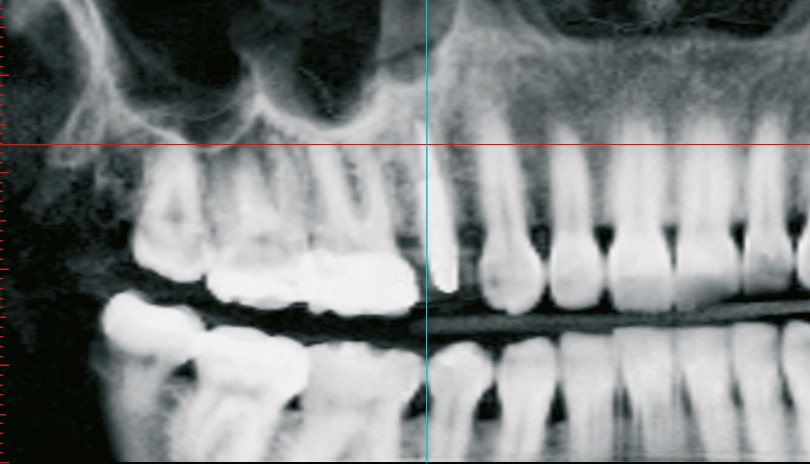

Um einen sinnvollen prothetischen Einschub unter optimaler Nutzung des Knochenangebots gewährleisten zu können, entschied man sich für eine teilnavigierte Aufbereitung des Implantatbetts. Mit der digitalen Planung sollte auch direkt nach der Implantatinsertion Primärstabilität gewährleistet werden, die für eine provisorische Sofortversorgung unerlässlich ist [8]. Als Implantat wurde das im Rahmen einer prospektiven, klinischen Langzeitstudie erprobte yttriumstabilisierte, einteilige Zirkondioxidimplantat ceramic.implant (vitaclinical, Bad Säckingen, Deutschland) ausgewählt, um der Patientin im Langzeitverlauf größtmögliche Sicherheit zu bieten. Das Implantat ist seit fünf Jahren dokumentiert und zeigt hier stabile Knochen- und Weichgewebsverhältnisse. Die Dreijahresdaten wurden bereits publiziert [9].

Um eine dreidimensionale Planung vornehmen zu können, wurde ein DVT erstellt und die Bilddaten wurden in die Planungssoftware 3Shape Implant Studio (3Shape, Kopenhagen, Dänemark) transferiert. Dort konnte die Implantation virtuell vorgenommen und in allen Raumdimensionen optimiert werden. Auf dieser Grundlage wurde eine Bohrschablone zur Teilnavigation hergestellt. Mittlerweile ist auch eine vollnavigierte, hülsenlose Implantation mit dem ceramic. implant möglich, das im Rahmen einer klinischen Studie eine noch präzisere Positionierung als bei den gängigen hülsengeführten Bohrschablonen zeigte [10].